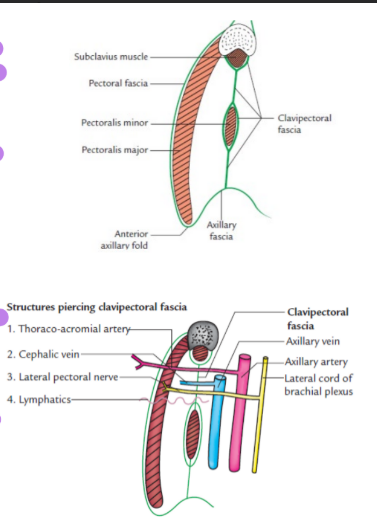

Clavipectoral fascia

Fibromuscular sheet situated deep to the clavicular portion of pectoralis major

Vertically- superiorly splits to enclose subclavius muscle and attached to clavicle

Horizontally- medially attached to 1st rib, costocoracoid ligament

Laterally- attached to coracoid process and blends with coracoclavicular ligament

Pierced by- lateral pectoral nerve, cephalic vein, thoracoacromial vessels and lymphatics